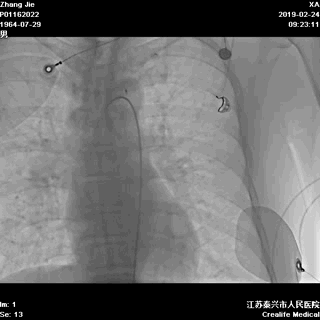

三、主动后适应操作

为了减轻心肌的再灌注损伤,我们进行了主动优化后适应操作:

导丝通过病变

09:04:34 导丝通过闭塞的病变进入前降支

09:07:22 球囊定位闭塞处,行初次PTCA

09:08:22 开放血流,10秒之内主动打起球囊堵闭血流

其后,进行了五轮后适应操作,初步结果如下:

左冠恢复前向血流

调整对角支导丝至前降支